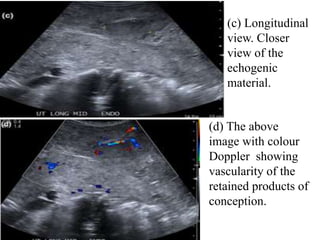

(c) Longitudinal

view. Closer

view of the

echogenic

material.

(d) The above

image with colour

Doppler showing

vascularity of the

retained products of

conception.

(c) Longitudinal view. Closer viewof the echogenic material. (d) The above image with colour Doppler showing vascularity of the retained products of conception.